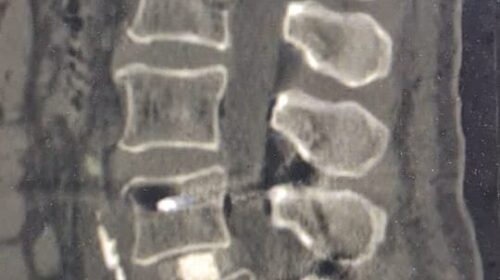

“Fueron tres tipos de exposiciones. Una de ellas es la cirugía en vivo, donde realizamos dos procedimientos en pabellón, acompañados por destacados especialistas, el Dr. Carlos Zanardi, presidente de la Sociedad de Neurocirugía de Buenos Aires, Argentina y el Dr. Cristiano Meneses, director del Instituto de Columna de Brasil”, precisó el Dr. Muñoz.

A continuación, compartimos las fotografías enviadas por el Dr. Avaria a la Sociedad de Neurocirugía de Chile: